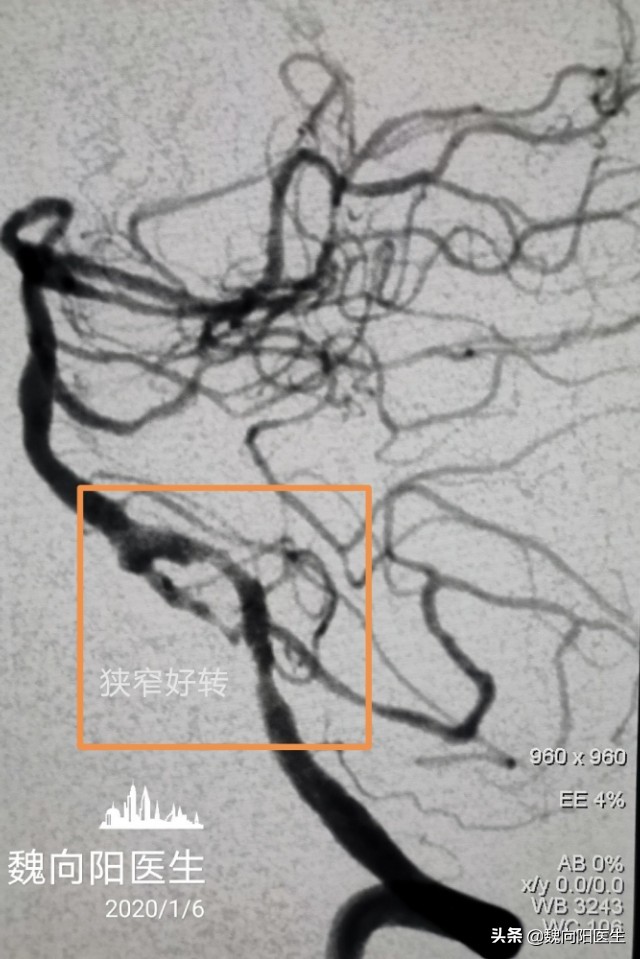

扩张之后狭窄病变明显好转,分别给予两狭窄处置入两枚支架(APPOLO 2.5×13mm和ENTERPRISE 4.5×22mm)。

再次造影:狭窄明显缓解。撤出导丝导管系统,手术结束。

术后患者头晕头昏症状明显好转。